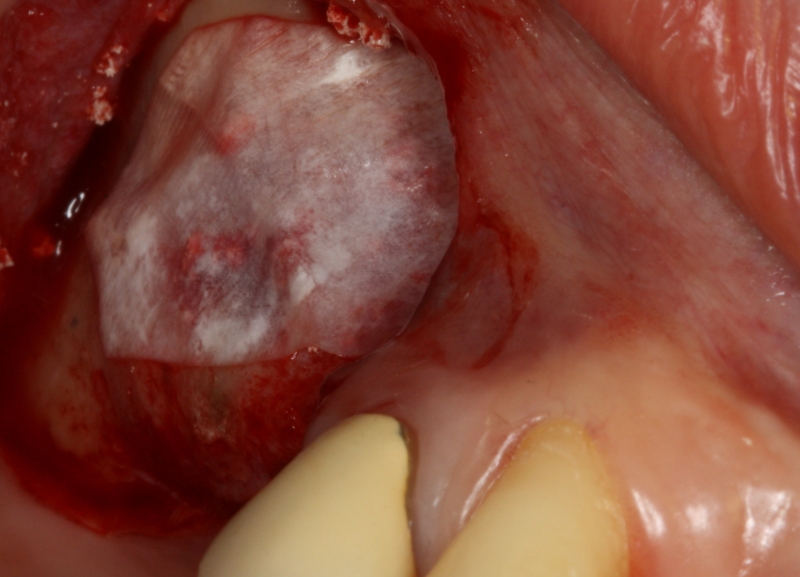

03/20 - Lateral sinus window prepared and Schneiderian membrane protected with a Jason® membraneGBR with maxresorb® & Jason® membrane - Prof. Dr. Dr. D. Rothamel